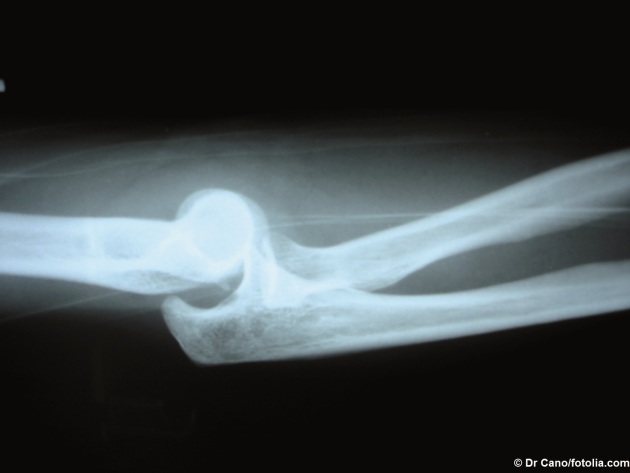

1. Indiquer le type de traumatisme visible sur la photo ci-dessous.

Le type de traumatisme visible sur la photo est une luxation (déboitement des os du coude).